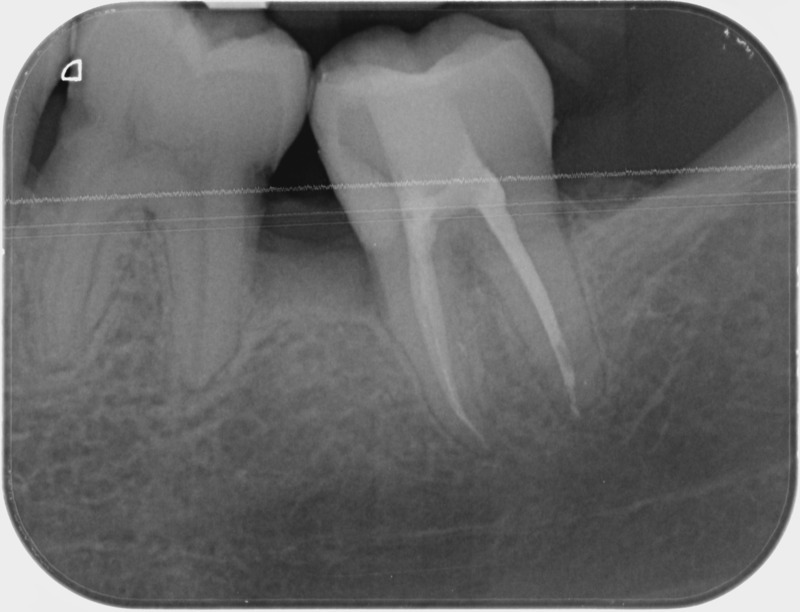

Avant

Après

• Reprise de traitement endodontique : La manœuvre consiste à retourner à l’intérieur des racines d’une dent déjà traitée. Il arrive occasionnellement qu’une nouvelle inflammation se déclare suite à une reprise de carie ou une fracture de la dent, ou si le premier traitement endodontique est incomplet. Après s’être assuré que la dent lésée était conservable, il convient de désinfecter de nouveau le réseau canalaire parfois très complexe. La nouvelle obturation des canaux devra être protégée aussi rapidement que possible pour éviter une éventuelle contamination bactérienne.